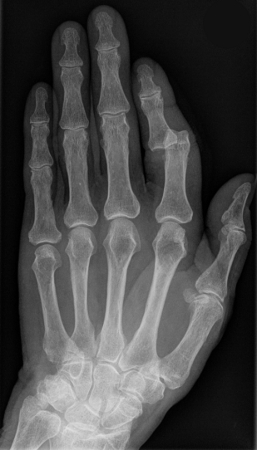

Radiografia mostrando luxação da articulação interfalângica proximal, dedo indicador esquerdo

Hellerhoff, CC BY-SA 3.0 via Wikimedia Commons